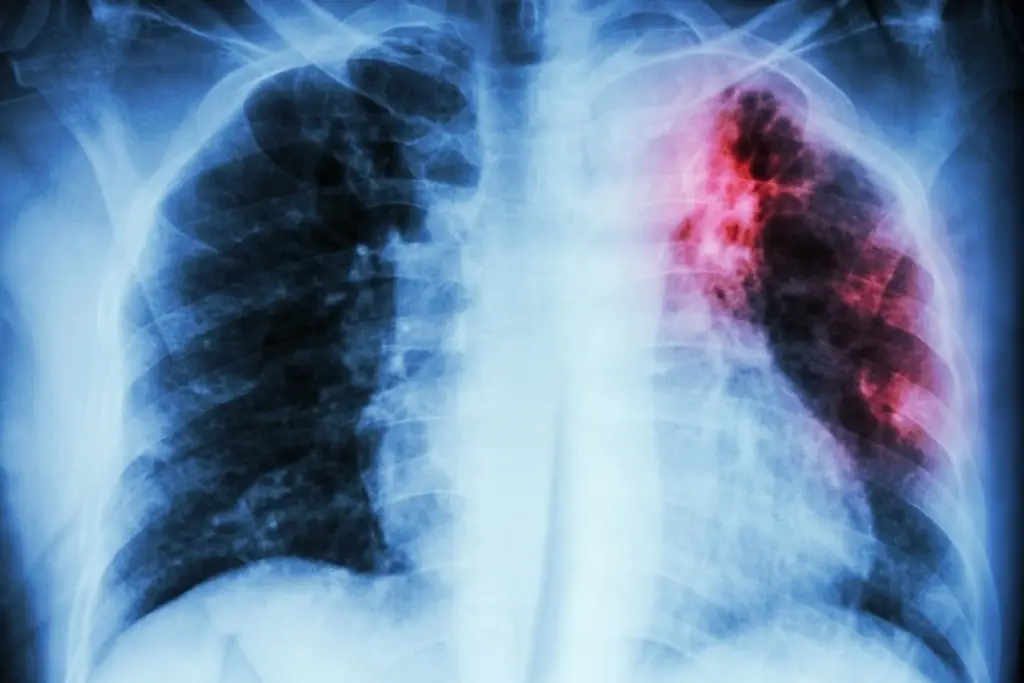

En Veracruz reprochan falta de atención a personas con VIH y tuberculosis

Imagen En Veracruz reprochan falta de atención a personas con VIH y tuberculosis

En los últimos seis años, en los hospitales públicos ha habido una desatención a personas contagiadas con VIH que a su vez desarrollan tuberculosis, señaló Patricia Ponce Jiménez, integrante del Grupo Multisectorial en VIH-SIDA.